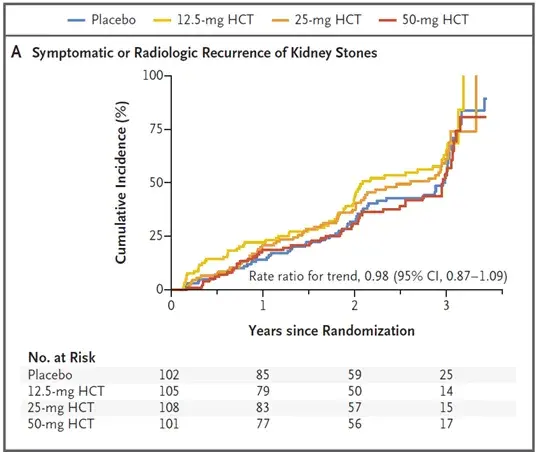

Hidroclorotiazida na nefrolitíase: devemos parar o uso?

Hidroclorotiazida na nefrolitíase: devemos parar o uso?Com esse novo estudo devemos repensar o uso da hidroclorotiazida como tratamento padrão da litíase renal